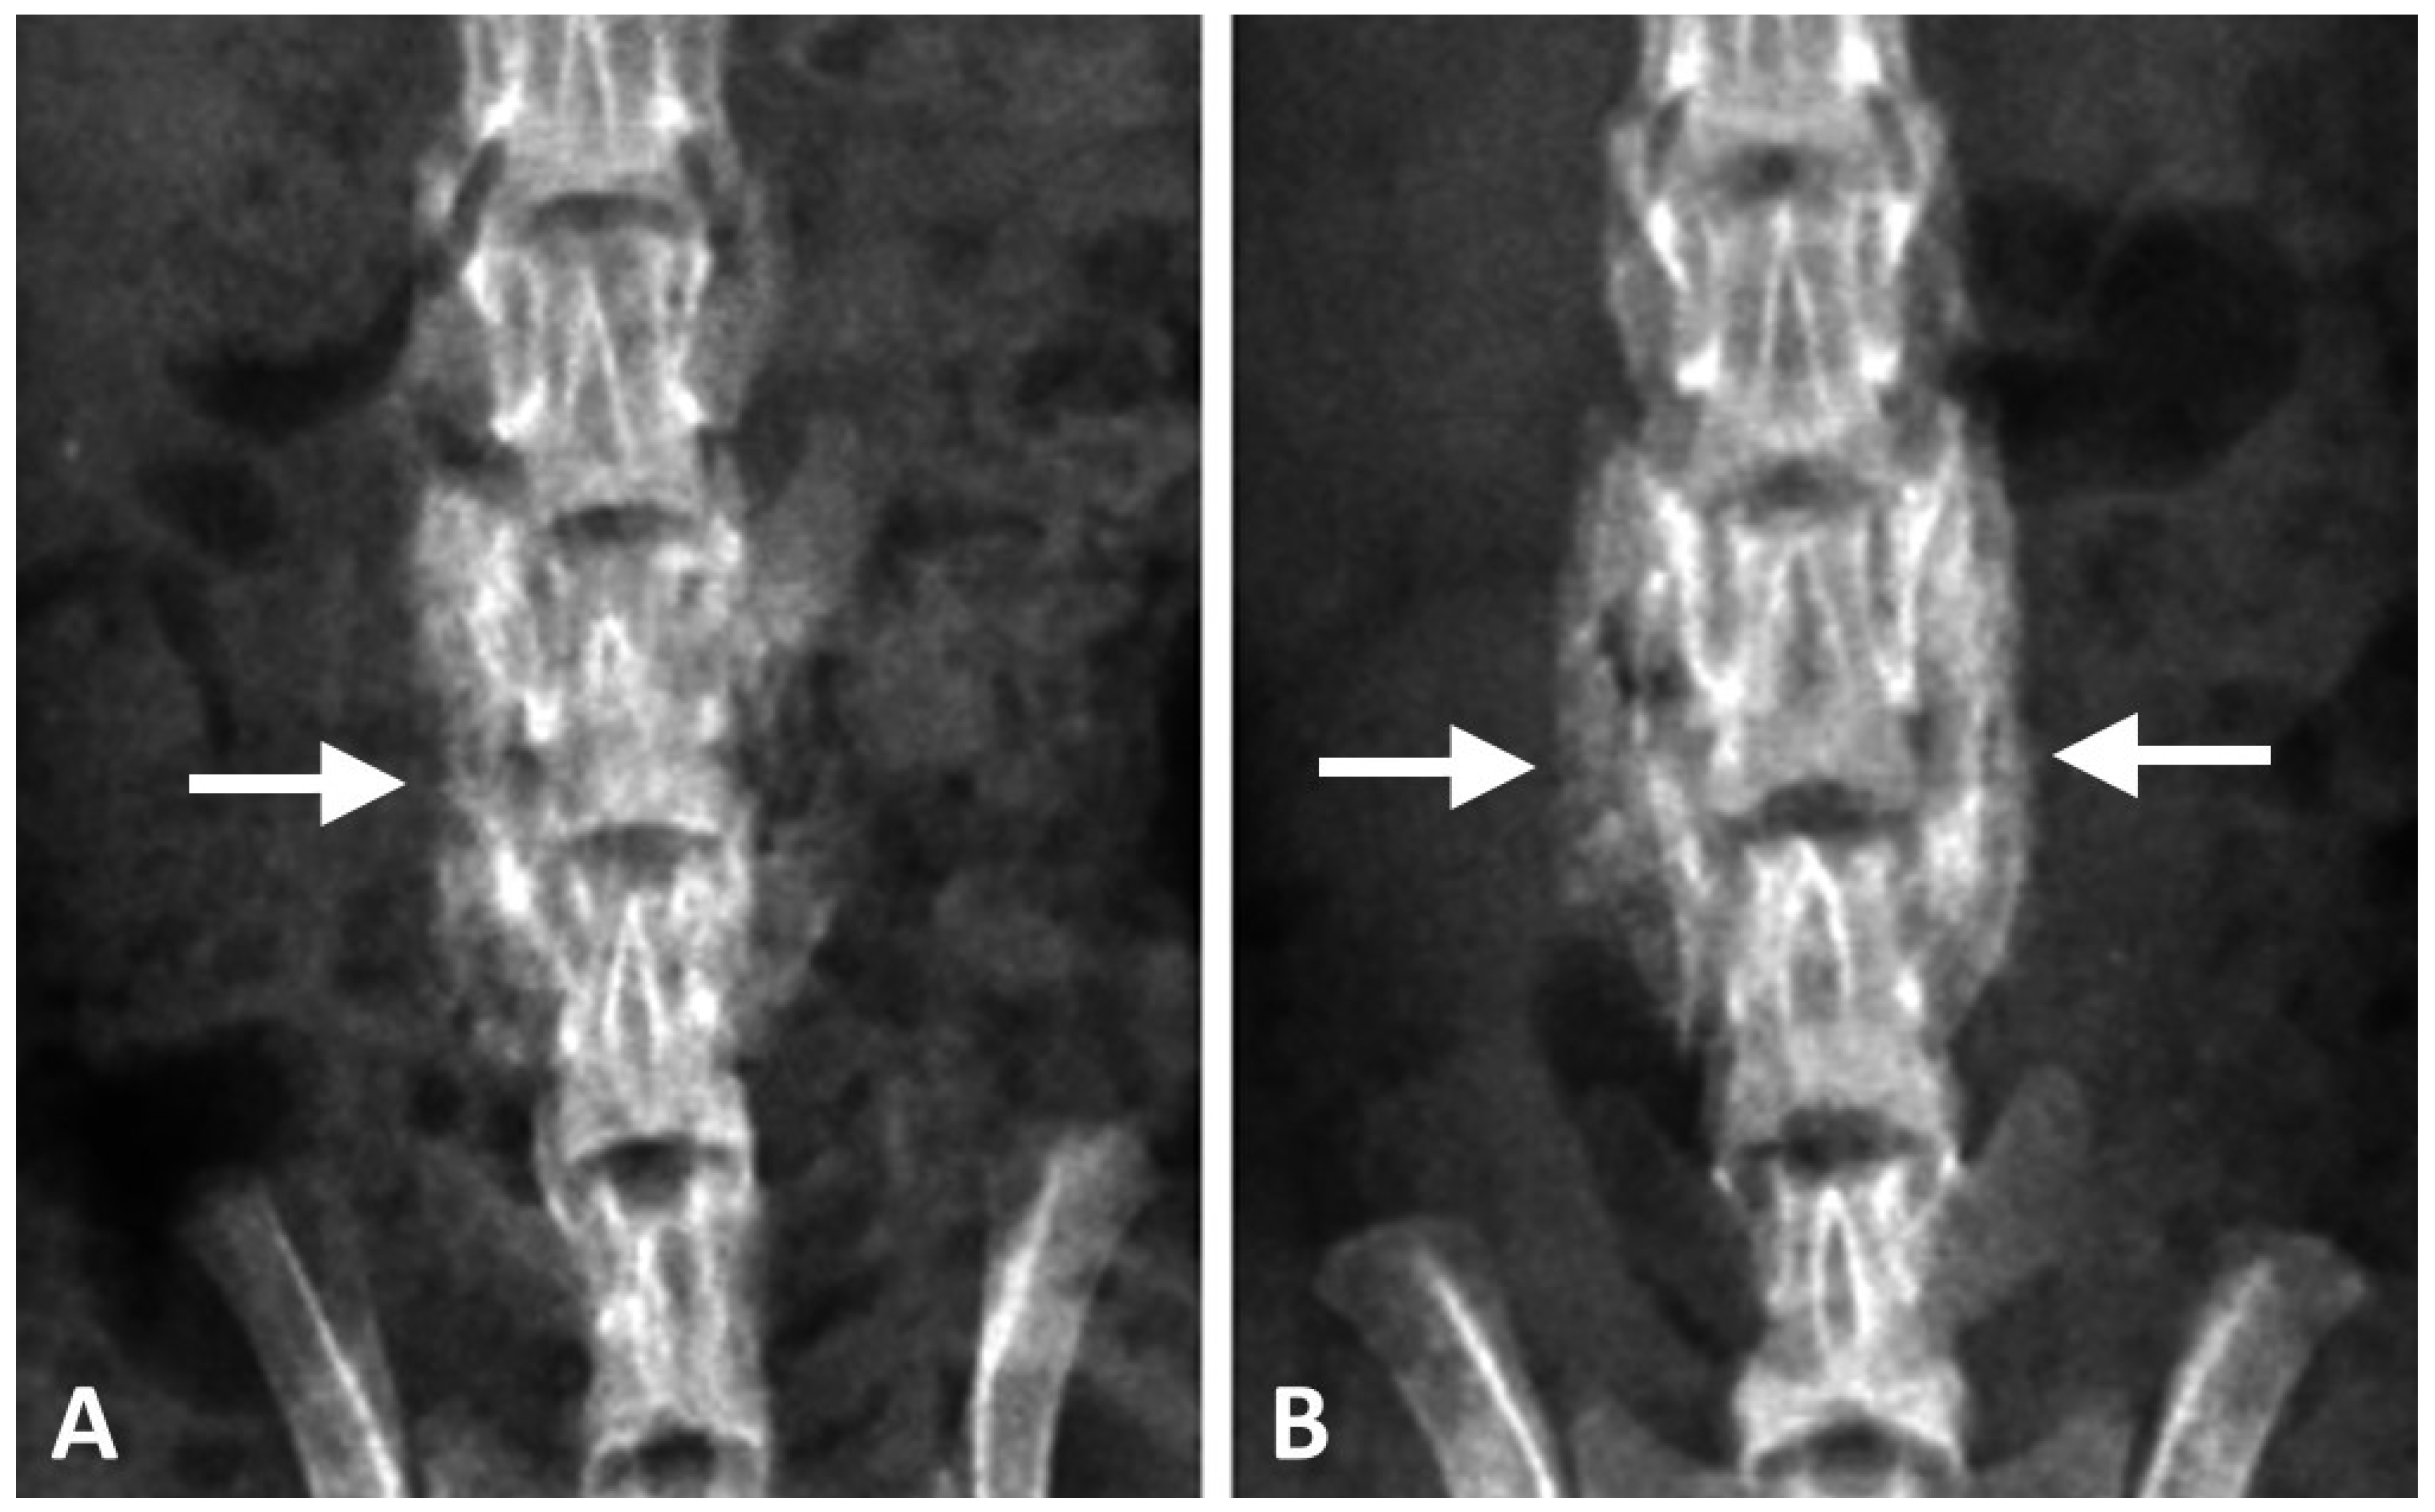

3.4. Histology

We noted that the control DCP-rich CPC grafts readily dropped off from the implantation site during specimen preparing procedures, including during the dehydration and cutting steps (Figure 7, left panel). The observed cavities indicate that the control DCP-rich CPC graft did not transform into new bone to an appreciable extent, and therefore, was not well-fused to the vertebrae body. The lack of adhesive force resulted in the grafts being easily washed out or dropped off. Conversely, more tissue bridging was present at the interface between new bone formation and bone graft in the DCP-rich CPC supplemented with 0.4 mL collagen group one to four weeks postoperatively than in the control group (Figure 7). Specifically, at postoperative week 1 there was no significant difference observed between the two groups. At week 2, the graft-bone junction was wider in the control group than in the DCP-rich CPC supplemented with collagen group with no other observed differences between groups. At weeks 3 and 4, new bone formation as well as activated osteoblasts and osteoclasts were noted in the DCP-rich CPC supplemented with 0.4 mL collagen group, which was not observed in the control group (Figure 8).

Figure 7. Representative histological coronal sections between the L4 and L5 transverse processes stained with haemotoxylin and eosin. (A,C,E,G) represented 1–4 weeks post-surgery of DCP-rich CPC group (100×). (B,D,F,H) represented 1–4 weeks post-surgery of DCP-rich CPC supplemented with 0.4 mL collagen group (100×). Scale bar = 100 μm. Abbreviation: G, implanted graft; H, host bone; I, interface between host bone and implanted graft; NB, new bone formation.